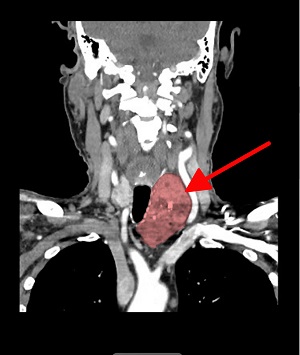

“Ken’s goitre was the size of a big orange, about 7cm, and was especially large on the left side, extending into his chest and compressing his airway,” Dr Meade said.

Pictured left: A scan of Mr Bruce's goitre.